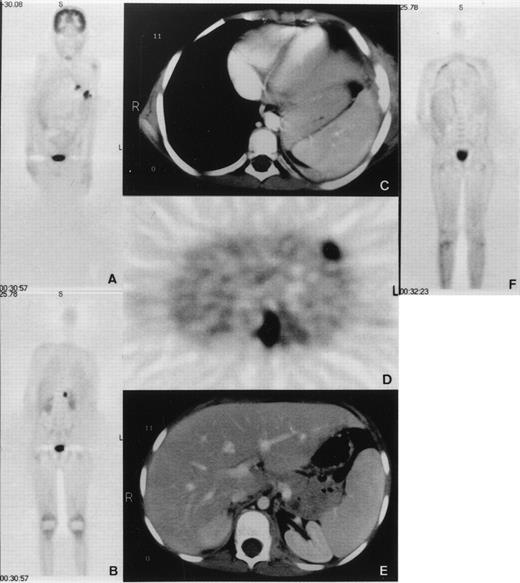

An 8-year-old boy with X-linked CGD (G828→A mutation in exon VIII resulting in a premature translation stop at amino acid position 272 and complete gp91-phox deficiency) was hospitalized because of pneumonitis. The patient had been under cotrimoxazole prophylaxis since the diagnosis at 8 months of age, and additionally under itraconazole prophylaxis since 3 years of age. No serious infections occurred until the age of 7 years when he developed a lingula pneumonitis after having stopped itraconazole for 4 weeks. After 5 months of unsuccessful treatment with various antibiotics, cultures taken from bronchoalveolar lavage showed growth of Aspergillus nidulans (A nidulans). The patient was treated for another 5 months with conventional amphotericin-B and γ-interferon, without improvement. Lingulectomy was performed with subsequent reisolation of A nidulans from excised lung tissue and pleural swabs. All isolates were susceptible to amphotericin-B and itraconazole, as determined by broth dilution method (MIC = 0.25 mg/L for conventional amphotericin, 0.25 mg/L for itraconazole, 1 to 2 mg/L for liposomal amphotericin B; AmBisome; Nexstar, San Dimas, CA). A second infectious agent, Actinomyces viscosus (A viscosus), was also repeatedly isolated from the previous bronchoalveolar lavage as well as from that performed during lingulectomy. These isolates were all susceptible to ciprofloxacin (MIC = 3 mg/L). The patient was administered liposomal amphotericin B (8 mg/kg/d) together with γ-interferon after surgery. He was treated with ciprofloxacin (20 mg/kg/d) since the first isolation of A viscosus. Two months after lingulectomy and while under this treatment, the patient developed persistent fever, tachydyspnoea, and severe lumbar pain. Whole-body positron emission tomography (PET) using F18-fluorodeoxyglucose (FDG) demonstrated five hypermetabolic foci (Fig 1). Four of these were pulmonary consolidations, one directly extending to the adjacent chest wall with osteolytic changes of the sixth rib leading to fistula formation into the skin. The fifth focus was a psoas abscess causing the excruciating pain and showed A nidulans on computed tomography (CT)-guided needle puncture. All PET lesions were seen in the corresponding CT images. There was no epidural extension as shown by CT and PET. These findings demonstrated that the conservative treatment had been unsuccessful. We elected to perform an emergency BMT from the HLA-genoidentical sister of the patient.

(A and B) Coronal emission FDG-PET scan before BMT. PET shows multiple inflammatory lesions in the lungs and an inflammatory focus in the upper left psoas with an intense FDG uptake. Physiologic high FDG uptake is seen in the brain, kidneys, and bladder. (C, D, and E) Axial transmission corrected FDG-PET image and corresponding CT images. Both PET and CT show inflammatory lesions in the left lung invading a rib and in the left psoas. (F) Coronal emission FDG-PET scan 3 months after BMT. Hypermetabolic lesions have disappeared.

The clinical course was surprisingly good with healing of the fistula over the rib and normalization of C reactive protein (CRP) on day 11 post-BMT (Fig 3). Cough disappeared after the third week. Fever persisted during the earlier weeks probably because of infection and afterwards, possibly due to GVHD. Starting on day 49, the patient developed grade III liver and grade I skin GVHD. In addition to cyclosporine-A, he was administered anti–interleukin-2 (IL-2) monoclonal antibodies (MoAb) (BB-10, BT 563, Leucotac; Biotest, Othmarsingen, Switzerland) at 0.4 mg/kg/d intravenously (IV).26 Steroids were excluded from the GVHD treatment because of their deleterious effects on PMN functions.27 28 The anti–IL-2 MoAb was administered daily until day 95 and every other day until day 109. Significant regression of the infiltration in CT and disappearance of the active inflammatory sites in PET were observed 3 months post-BMT (Fig 1). The cellular immune recovery was full at 4 months. Liposomal amphotericin-B was then replaced by oral itraconazole at 10 mg/kg/d. The patient was discharged at 5 months after BMT. At the time of preparation of this report, the patient, 2 years post-BMT, is doing well with no sign of infection or GVHD. He was substituted with IV immunoglobulins monthly until 12 months post-BMT. The karyotype analysis done on the mononuclear cells from peripheral blood showed 100% donor chimerism. The granulocyte function studies also demonstrate that they are of donor origin (Table1 and Fig 4).